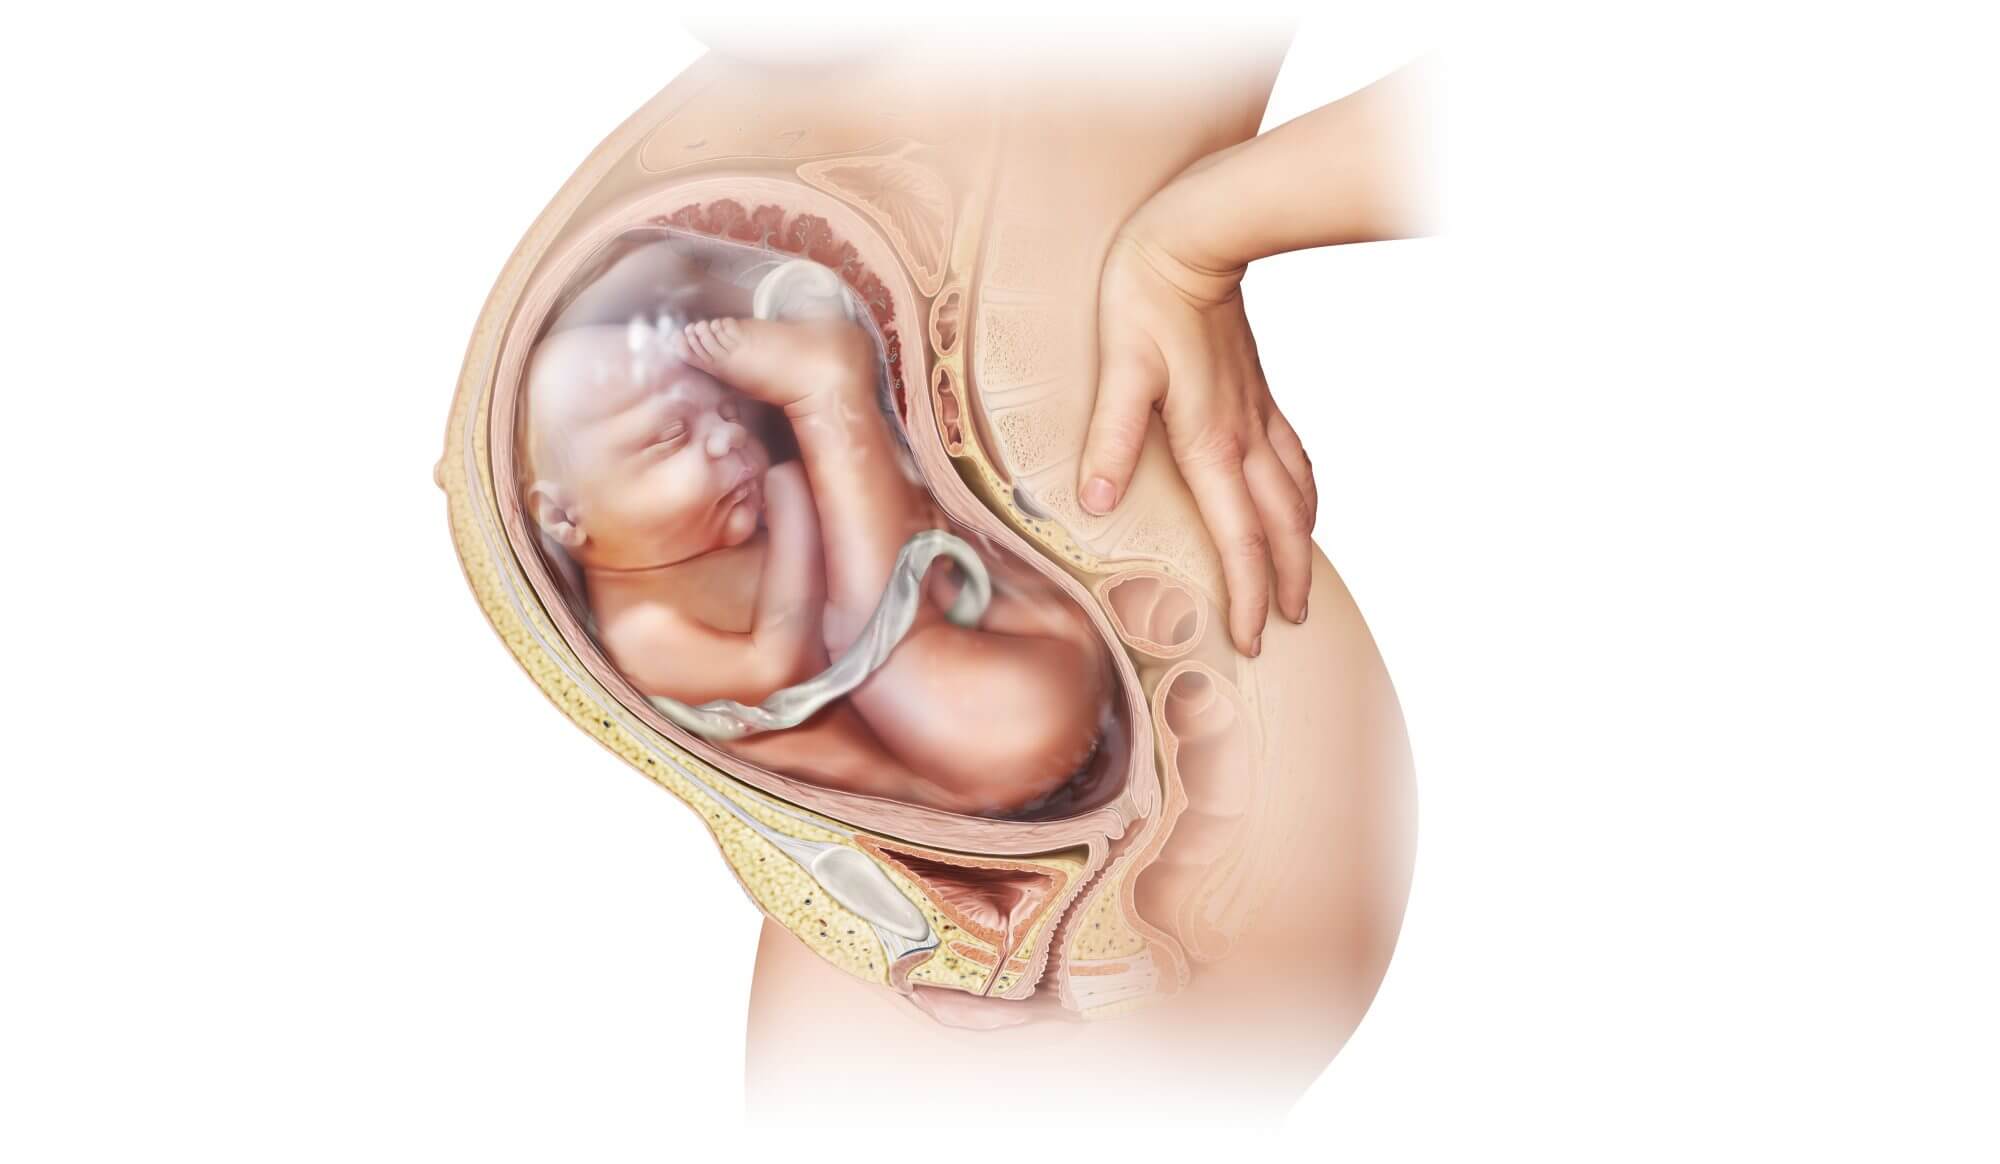

Многоводие при беременности: симптомы и лечение